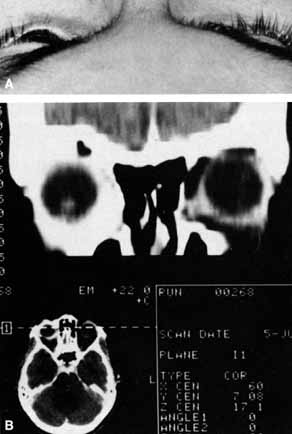

A 70-year-old woman presented with a 6-month history of progressive diplopia and ptosis. She demonstrated complete right third, fourth, and sixth cranial nerve palsies, and hypesthesia of cranial nerve V1 (Fig. 22A). The right pupil was dilated. Computed tomography (CT) disclosed an intracavernous aneurysm (see Fig. 22B).

Fig. 22 A. A 70-year-old woman with complete right third, fourth, and sixth cranial nerve palsies. Hypesthesia of cranial nerve V1 was also present. B. CT scan demonstrates an intracavernous aneurysm (arrow).

The so-called superior orbital fissure syndrome occurs when an infiltrative, inflammatory, or ischemic event occurs within the superior orbital fissure, but not in the orbital apex.4 A complete superior orbital fissure syndrome occurs when all the neurovascular components passing through the superior orbital fissure are damaged, producing a total ophthalmoplegia, ptosis, and anesthesia of cranial nerve V1 (see Fig. 22A). The pupil may be dilated, miotic, or midposition and fixed, depending on the balance of parasympathetic and sympathetic damage. The superior ophthalmic vein, best seen on CT, may be dilated if venous outflow from the orbit is obstructed. Clues to venous outflow obstruction are increased intraocular pressure, fullness of the upper eyelid, and hyperemia of the deep Tenon's vessels. Ophthalmoscopically, the retinal veins may be dilated. The effect of a lesion in the superior orbital fissure or the anterior cavernous sinus cannot be differentiated clinically (see Fig. 22B). When the posterior cavernous sinus becomes involved, hypesthesia of cranial nerve V2 may also be present.

The only difference between a superior orbital fissure syndrome and an orbital apex syndrome is the presence of visual loss caused by optic nerve involvement. Visual acuity, color vision, or the visual field are abnormal. An ipsilateral relative afferent pupil defect is present.